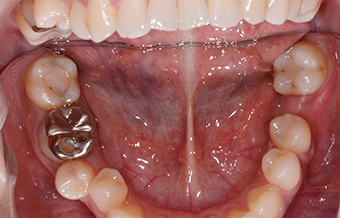

CASE